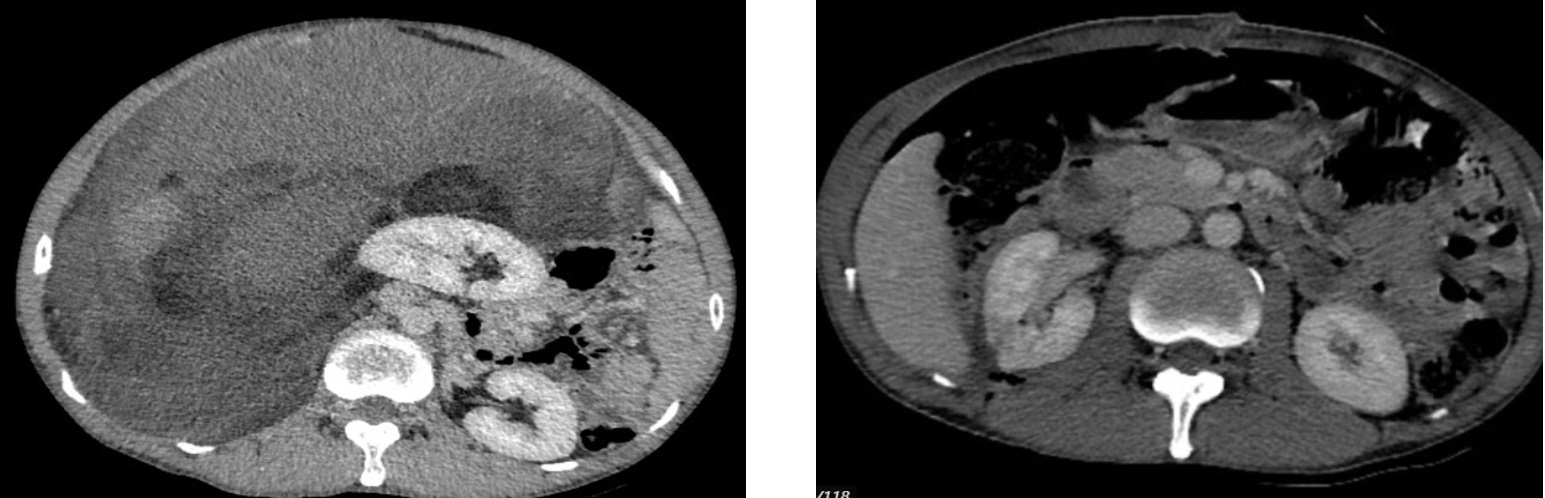

Hình ảnh chụp chụp cắt lớp vi tính ổ bụng sau phẫu thuật 1 tuần (03/2025): Hình ảnh sau mổ u sau phúc mạc bên phải, hiện thấy tụ dịch-khí khoang sau phúc mạc kèm ống dẫn lưu bên trong. Khí tự do ổ bụng (sau mổ). Khí trong mạc treo ruột. Dịch tự do ổ bụng

Hình 3. Hình ảnh chụp cắt lớp vi tính ổ bụng: Hình ảnh sau mổ u sau phúc mạc bên phải, hiện thấy tụ dịch-khí khoang sau phúc mạc (sau mổ 1 tuần)

Hình ảnh so sánh khối u trước và sau phẫu thuật

Trước phẫu thuật: Hình ảnh khối u lớn sau phúc mạc. Sau phẫu thuật 1 tuần: hiện thấy tụ dịch-kích thước khoảng 253x127mm, ngấm thuốc khí khoang sau phúc mạc sau tiêm, đè đẩy các cấu trúc lân cậnn.